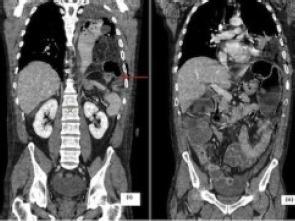

Diaphragmatic hernias are usually congenital, and they usually occur in the neonatal group. They do occur in the adult population, albeit very rarely. We present a case of an adult male patient with complications as a result of a congenital diaphragmatic hernia. The patient presented with atypical abdominal pain and respiratory distress. Radiological investigations confirmed a left hydropneumothorax as well as large bowel obstruction secondary to herniation of the omentum and transverse colon through a congenital defect in the left hemi-diaphragm. He had a laparotomy, which confirmed the radiological findings and a perforated transverse colon. He went onto have an extended right hemicolectomy and end-ileostomy; his left hemithorax was lavaged and a thoracostomy tube was inserted. He recovered well, except that he developed an empyema postoperatively for which he required a thoracotomy and decortication. He made good recovery following this and was discharged home nine days following his initial laparotomy.

膈疝通常是先天性的,多见于新生儿群体。成人也会发生膈疝,不过极为罕见。我们报告一例成年男性患者,因先天性膈疝出现并发症。该患者表现为非典型腹痛和呼吸窘迫。影像学检查证实存在左侧液气胸以及因大网膜和横结肠通过左侧半膈肌先天性缺损疝出导致的大肠梗阻。患者接受了剖腹探查术,术中所见证实了影像学检查结果,还发现横结肠穿孔。随后他接受了扩大右半结肠切除术和末端回肠造口术;对其左胸腔进行了灌洗并插入了胸腔引流管。他恢复良好,只是术后并发了脓胸,为此又接受了开胸胸膜剥脱术。此后他恢复良好,在初次剖腹探查术后九天出院。